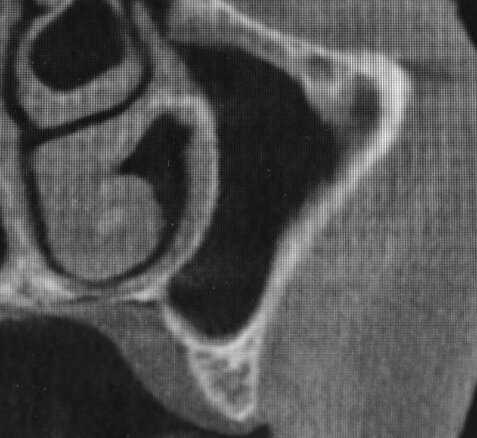

In seguito all’intervento di rialzo di seno mascellare con contestuale GBR è stata eseguita la radiografia ortopanoramica che mostra il corretto riempimento dell’area atrofica del seno mascellare con granuli cortico-spongiosi di osso di origine bovina. Al controllo dopo tre settimane i tessuti molli dell’area trattata risultano perfettamente guariti. La TC Dentalscan effettuata dopo 6 mesi per il controllo della zona rigenerata evidenzia la perfetta guarigione della zona con aumento dello spessore osseo di 5 mm e dell’altezza ossea di 11 mm.